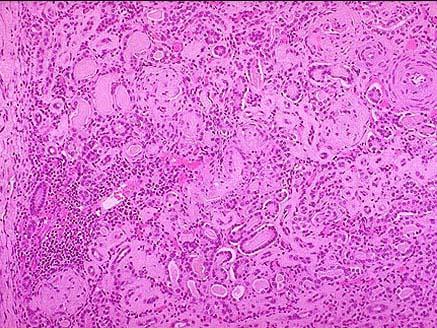

问题 老年女尸,双肾大体如图所示,镜下如图所示,关于该疾病下列说法正确的是 ( )

选项 A.为各种不同类型肾炎发展的最后阶段 B.肾小球不会发生玻璃样变和硬化 C.为老年人肾的正常改变 D.常引起急性肾功能衰竭 E.通过治疗,该疾病可以逆转

答案 A